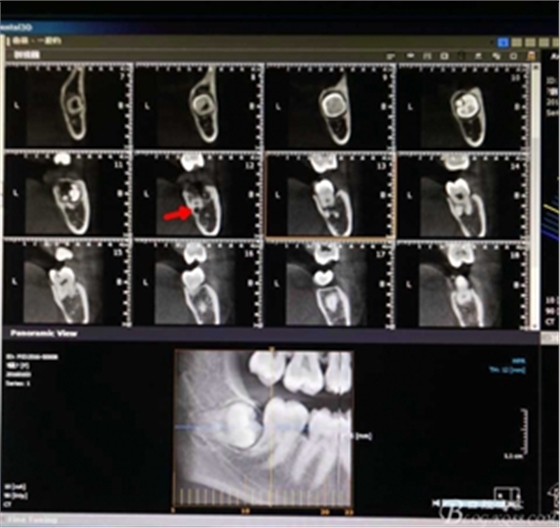

圖2.術(shù)前的cbct檢查:38牙冠周?chē)泄墙M織覆蓋,下頜神經(jīng)管離38牙冠還有一定距離,在去除牙冠的時(shí)候,損傷神經(jīng) 的風(fēng)險(xiǎn)較小。38牙根舌側(cè)骨壁較薄。

圖3.冠向檢查:38牙根未進(jìn)入下頜管內(nèi),牙冠周?chē)醒滥矣啊?p style="text-align:center">

圖4.術(shù)前的CBCT縱剖面檢查:38牙根1/3緊鄰下頜管,看紅色箭頭。提示盡量不要斷根,如根尖折斷,取根導(dǎo)致下頜神經(jīng)損傷的風(fēng)險(xiǎn)加大